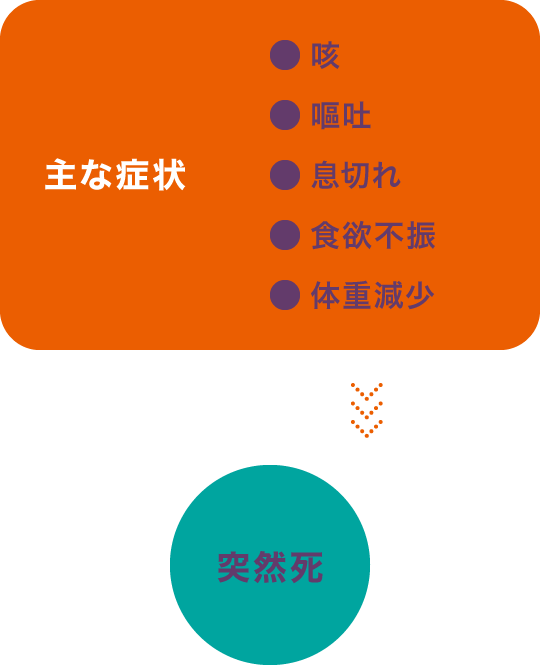

主な症状

- 咳

- 嘔吐

- 息切れ

- 食欲不振

- 体重減少

ねこのフィラリア症は、咳などの呼吸器症状や嘔吐が多く見られます。しかし、咳の症状はねこの喘息と誤解されやすく診断が遅れてしまうことも。診断が遅れ、病状が悪化すると突然死を招く場合があります。